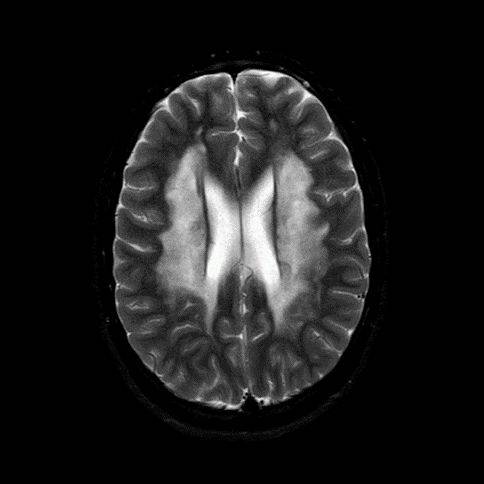

- A) Aksiyel T2A ve koronal T2A sekanslarda sentrum semiovale, korona radiata ve bazal ganglionlar düzeyinde bilateral frontoparietal derin periventriküler beyaz cevherde birleşme eğilimi gösteren hiperintens gliotik sinyal değişiklikleri (oklar) ve aksiyel T2A serilerde servikal spinal kordda posterior kolonda, lateral kesimlerde sinyal artımları (oklar) izlendi.

- LBSL, karakteristik radyolojik özelliklere sahiptir. MRG’de tipik olarak bilateral ve simetrik beyaz cevher sinyal değişiklikleri görülürken, subkortikal U lifleri, internal kapsülün posterior kolları, trigeminal sinir traktları, serebellum, korpus kallozumun spleniumu, medulla oblongata ve omurilikteki dorsal kolonlar ile lateral kortikospinal traktlar genellikle korunur.

- Etkilenen bölgelerde T1’de hipointens, T2/FLAIR’da hiperintens sinyal değişiklikleri izlenir. DWI’de lezyonların periferinde kısıtlı difüzyon görülebilir. MRS’de beyaz cevherde laktat artışı saptanabilir, ancak bu her hastada mevcut değildir.